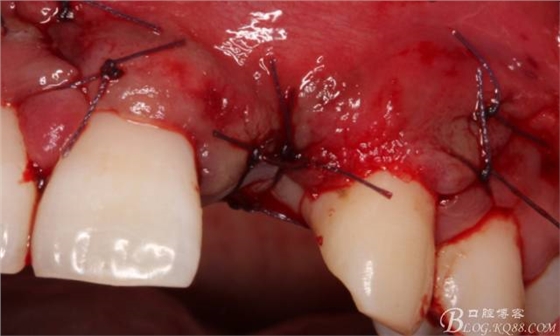

縫合。